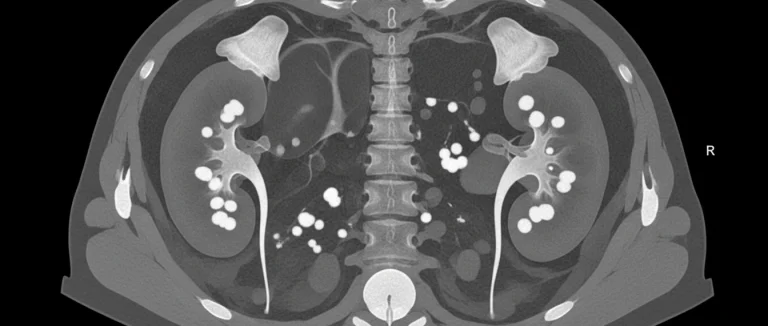

Современные подходы к диагностике позволяют точно определить размер, локализацию и состав камня, что критически важно для выбора оптимального метода лечения. В Лив Хоспитал применяется комплексный протокол, включающий:

- УЗИ почек – быстрый, безболезненный метод первой линии.

- КТ с контрастированием – «золотой стандарт» для оценки размеров и плотности камня.

- Рентгенография (рентген почек) – полезна при кальцийсодержащих камнях.

- Анализ мочи и крови – определение уровня кальция, оксалатов, уратов.

Диагностический протокол в Лив Хоспитал начинается с ультразвукового исследования почек – быстрого и безболезненного метода первой линии. При необходимости проводится КТ с контрастированием, считающееся «золотым стандартом» для точного определения размера, локализации и плотности камня. Рентгенография (рентген почек) полезна для выявления кальцийсодержащих камней. Дополнительно анализируют мочу и кровь, чтобы оценить уровень кальция, оксалатов, уратов и другие метаболические показатели, влияющие на образование камней.